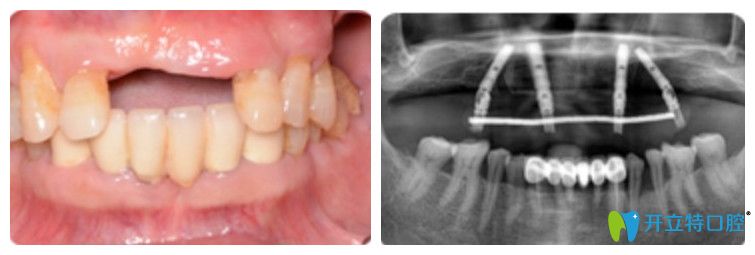

王先生在優(yōu)貝口腔做完種植牙前后圖

即刻用種植牙恢復(fù)半口好牙

王迪院長說即刻用種植牙并不是單純的種植技術(shù),還要從術(shù)前的全景數(shù)字化口腔檢查、口腔環(huán)境預(yù)評、牙槽骨條件測量等檢查形成專屬種植方案。通過各項(xiàng)檢查發(fā)現(xiàn):王叔佩戴假牙時間比較長,導(dǎo)致牙槽骨有點(diǎn)萎縮,剩下的那幾顆牙齒牙根也已經(jīng)松掉了,沒有保留的價(jià)值,需要先拔掉,然后做ALL—on—4即刻種植牙

王迪院長利用4顆種植體,兩顆種植體垂直植入牙槽骨內(nèi),另外兩顆采取傾斜角度植入牙槽骨內(nèi),然后在種植體的基臺安裝“拱形連橋”牙冠,實(shí)現(xiàn)半口牙種植。

王迪院長為王先生做的連橋牙冠

王先生半口牙種植前后的變化